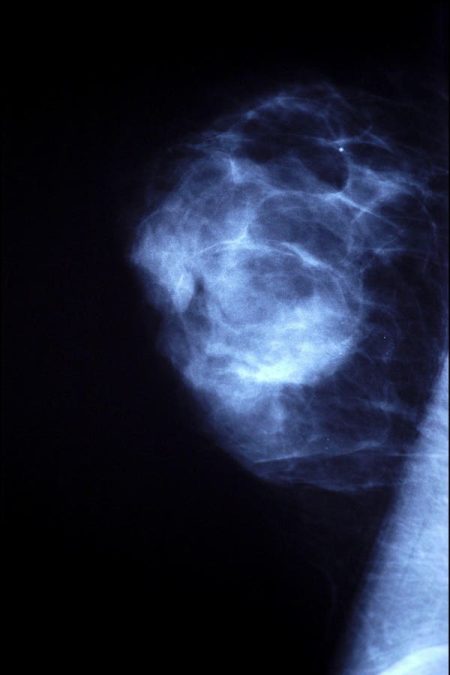

October is Breast Cancer Awareness Month, and public health professionals dedicate their efforts this month in promoting mammogram screening for…